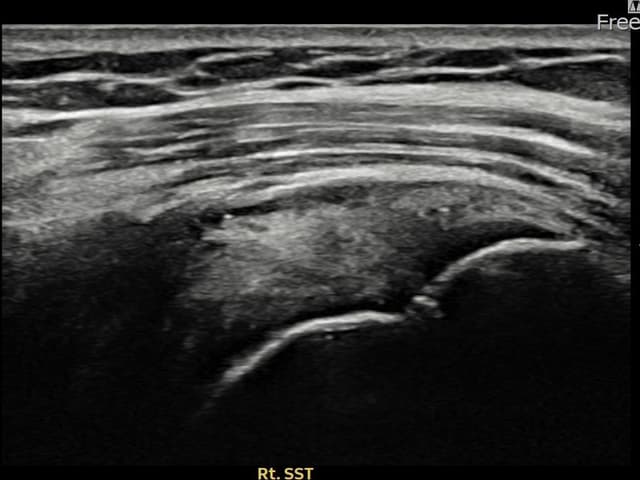

[촬영시기:22.09.05~22.12.08]

[어깨인대 축소봉합술] 우측 어깨 통증과 야간 통증으로 수면 장애가 있어 내원하셨습니다.